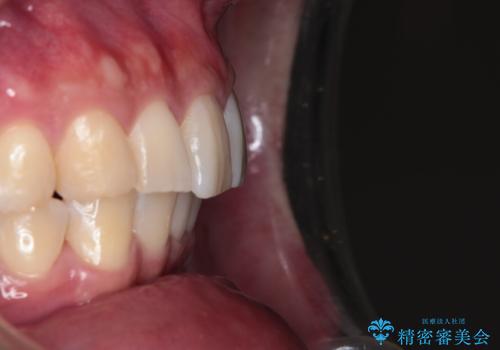

【インビザライン】短期間で出っ歯を治したい

- 出っ歯と口元の突出感が気になるということで来院されました。抜歯矯正も考えられますが、今回は早く終わらせたいという要望があり非抜歯での治療にしました。また遠方から来院されているため、来院回数のおさえられるインビザラインを選択しました。

非抜歯での治療のため、今回はスペース確保のために遠心移動とおもにIPRの処置を取り入れました。